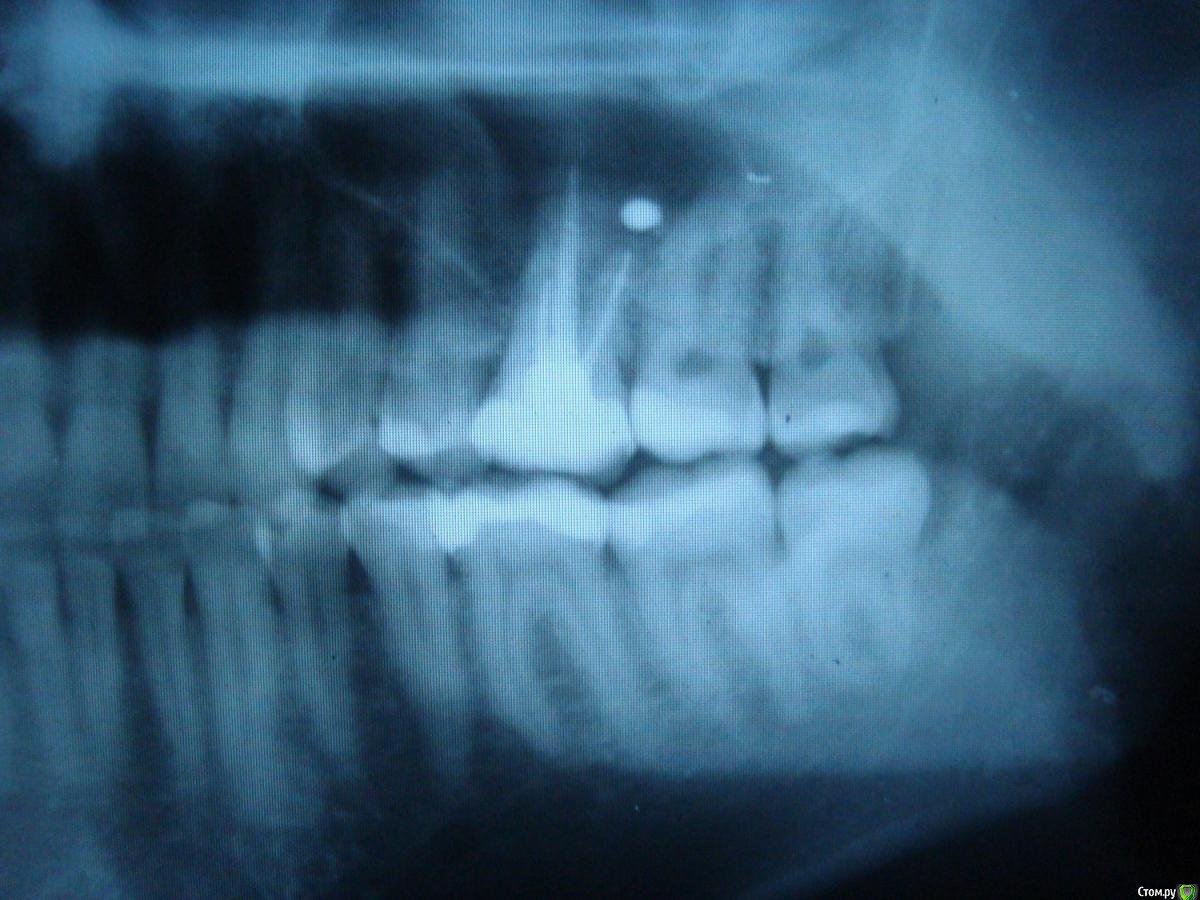

player543 Опубликовано 16 марта, 2015 Поделиться Опубликовано 16 марта, 2015 Здравствуйте.У меня иногда болит зуб при надавливании во время еды. Иногда несколько дней вообще не болит, в другой день при надавливании при каждом приеме пищи.Этот зуб был вылечен (пульпит) лет 7 назад, не помню делали ли рентген для проверки лечения.Эта нерегулярная боль при надавливании уже пару лет (и вроде бы не ухудшается). Помню что в течение года после лечения зуб болел при наклоне головы (но тоже не всегда). Прежде всего хочу разобраться в чем проблема зуба. Несколько стоматологов говорили что все из-за того, что пломбировочный материал попал в гайморову пазуху, предлагали идти к ЧЛХ и как-то там это "вычищать". Последний врач сказал что там канал до конца не заполнен и там живет инфекция. Почему-то сказал что нужно удалять зуб, а я не спросил почему.Ваше мнение в чем проблема зуба? И второе - как его лечить? Просто перелечивание каналов? Можно ли перелечить только 1 канал или только все сразу? Этот зуб был восстановлен более чем на 1/2 если это важно. Ссылка на комментарий

Гарриевич Опубликовано 16 марта, 2015 Поделиться Опубликовано 16 марта, 2015 Лечить можно двумя путями1- перелечивать все корневые каналы2- только каналы передне-щечного корня Ссылка на комментарий

red_butler Опубликовано 17 марта, 2015 Поделиться Опубликовано 17 марта, 2015 Для начала хорошо бы сделать Кт, и посмотреть верхнечелюстной синус. Далее повторное лечение с последующим протезированием. Точный объем лечения будет понятен в процессе.Показаний к удалению не увидел Ссылка на комментарий